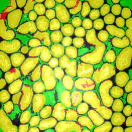

For visual evaluation we provide the segmentation results of the proposed method using two different datasets: and , sampled at different depths within the volumes. The first row shows original microscopy images , , and from and the second row displays the segmentation results corresponding to the first row. To better visualize the segmentation results, we highlighted individual tubules with different colors and overlaid them onto the original microscopy images. Similarly, the third row exhibits original microscopy images , , and from . Their corresponding segmentation results are shown in the fourth row. Note that the model which was trained on was used for during the inference stage. Although the shape, size, and orientation of tubular structures presented in are all different from , the proposed method can still successfully segment and identify individual tubules presented in as well as individual tubules in .